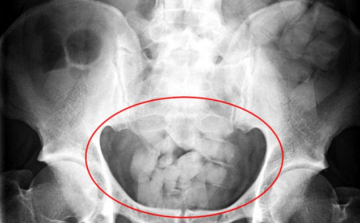

Egy kilogramm kokaint akart Magyarországra csempészni egy brazil férfi úgy, hogy száz kokainkapszulát nyelt le - közölte az Országos Rendőr-főkapitányság kommunikációs szolgálata kedden a rendőrség honlapján.

Kábítószer birtoklása miatt indított nyomozást a Készenléti Rendőrség Nemzeti Nyomozó Iroda egy 30 éves bissau-guineai férfi ellen, aki száztíz, kokaint tartalmazó kapszulát csempészett a gyomrában Magyarországra